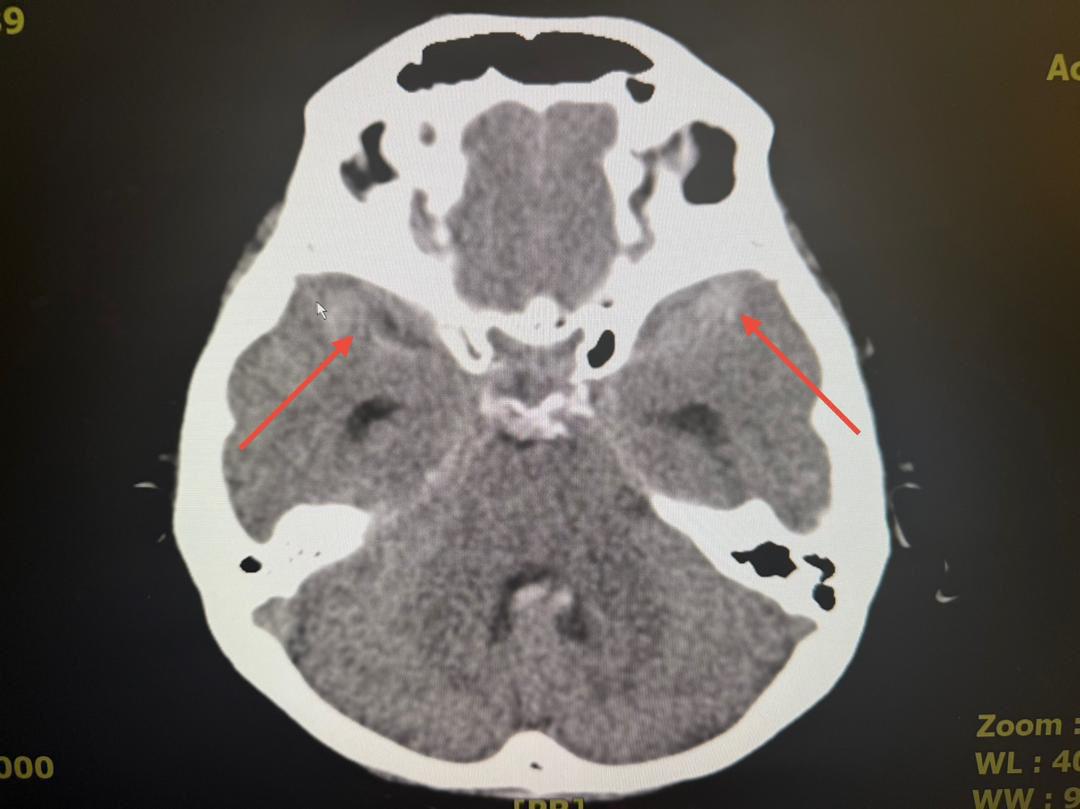

“A 60-year-old female patient was referred to PCSH after experiencing a severe headache.

“With the hospital equipped with the latest angiogram technology, the medical team successfully conducted detailed imaging, which revealed a small 2mm aneurysm in the right middle cerebral artery, a potentially life-threatening condition if left untreated,” the statement said.

At PCSH, a Digital Subtraction Angiogram (DSA) confirmed the aneurysm’s presence.